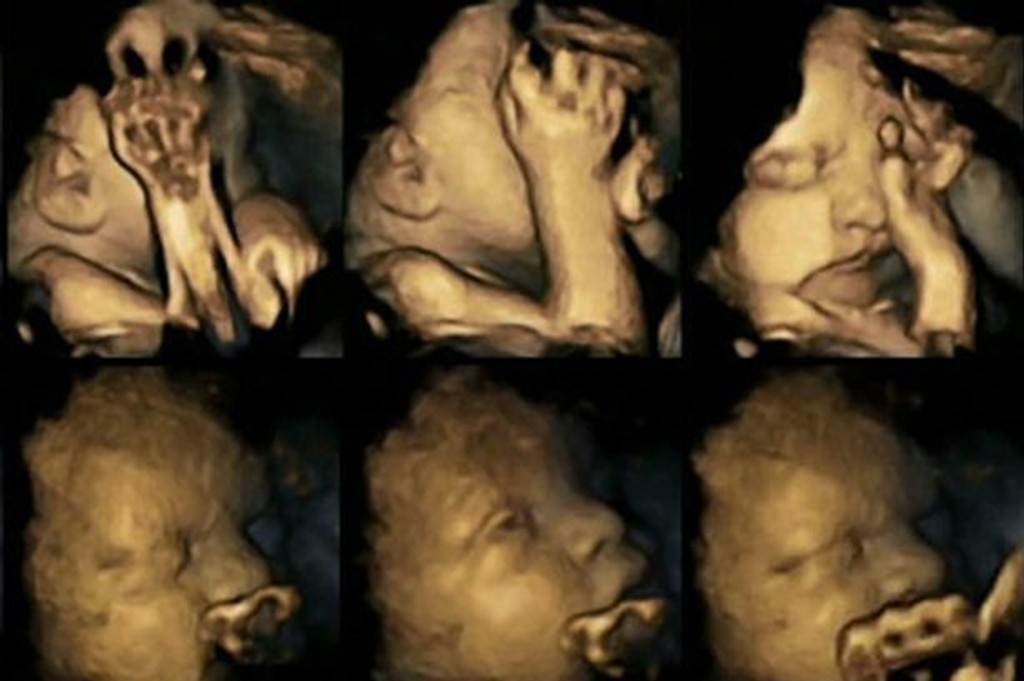

Ultrazvukové snímky ukazujú, aký vplyv má fajčenie na bábätko

Toto by malo ľahšie prinútiť tehotné fajčiarky odhodiť cigarety, ktoré zvyšujú riziko predčasného pôrodu, dýchacie ťažkosti a syndróm náhleho úmrtia bábätka.

Ultrazvukové 4D vyšetrenie je momentálne veľmi populárne. Rodičia tak môžu vidieť, ako ich bábätko vyzerá a ešte počas jeho pobytu v brušku môžu hádať, na koho sa viac podobá. Ale vedci sa ho rozhodli využiť aj na niečo iné. Doktorka Nadja Reissland preskúmala tieto snímky a zaznamenala tisícky drobných mimických pohybov v maternici. Pozrela sa aj na to, ako dieťatko reaguje na to, že jeho mama fajčí. Myslia si, že toto ľahšie prinúti tehotné fajčiarky odhodiť cigarety, ktoré zvyšujú riziko predčasného pôrodu, dýchacie ťažkosti a syndróm náhleho úmrtia bábätka.

Monitorovala 20 budúcich mamičiek v nemocnici Jamesa Cooka v Middlesbourghu. Z toho štyri tehuľky vyfajčili 14 cigariet denne. Študovala ich ultrazvukové snímky z 24., 28., 32. a 36. týždňa. Ich bábätká sa výrazne rýchlejšie pohybovali a stále si chytali tváričku či hlavu, čo bábätká nefajčiarok nerobia v takej miere. Čím viac sa blíži dátum ich príchodu na svet, tým menej to robia, píše mirror.co.uk.

Doktorka Reissland tvrdí, že deti fajčiarok môžu mať pomalší vývoj centrálneho nervového systému. Svojou štúdiou ich nechce démonizovať. Chce vyzvať k väčšej podpore tehotných fajčiarok, aby prestali. V súčasnosti fajčí vo Veľkej Británii 12 percent tehotných žien, až 20 percent v oblastiach Druhamu, Darlingtonu a Teesu.

Spoluautor štúdie Brian Francis z univerzity v Lancasteri tvrdí: "Technológia nám umožnila vidieť to, čo bolo donedávna skryté. Odhaľuje, ako fajčenie ovplyvňuje vývoj plodu. Je to ďalší dôkaz negatívnych účinkov fajčenia v tehotenstve."